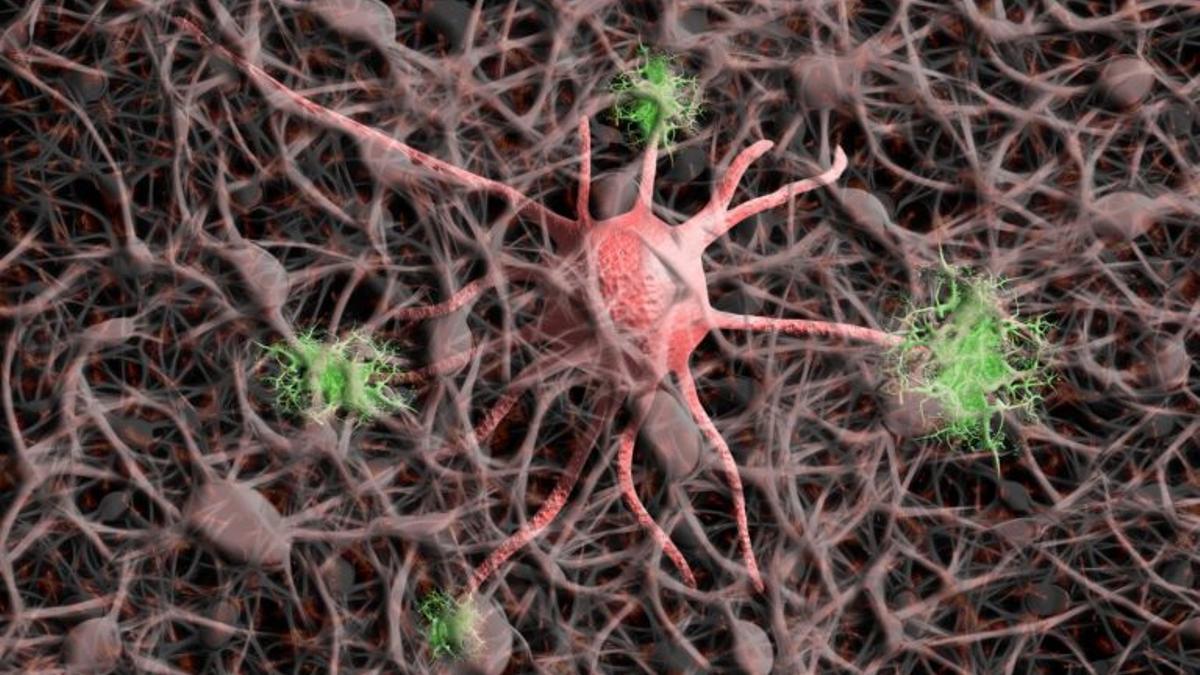

Reproducción de un cerebro humano.